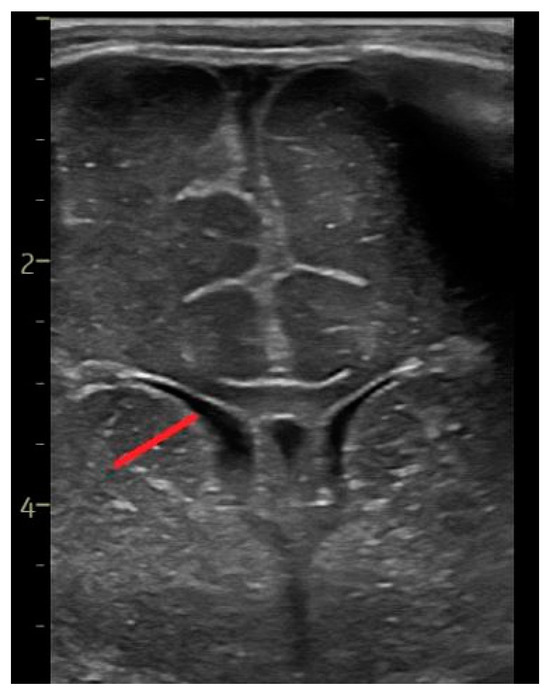

2.2. Head Ultrasound Measurements at TEA